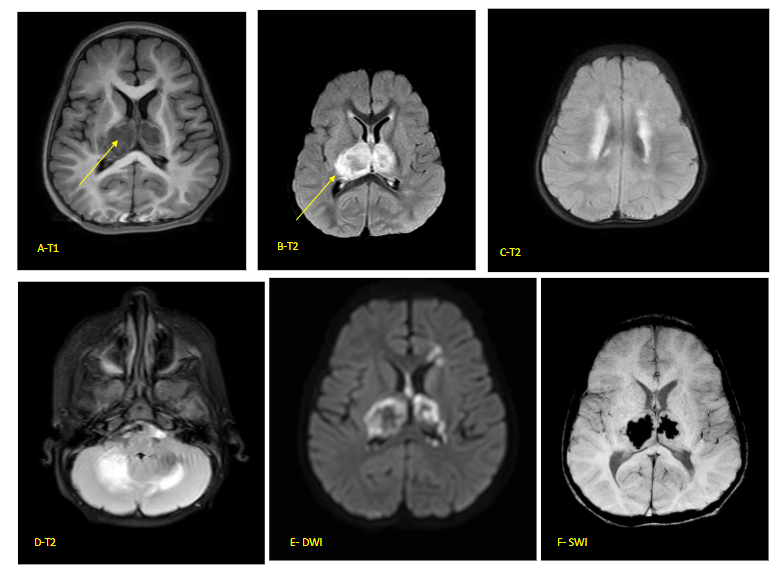

In ANEC/ANE1, there is involvement of bilateral thalami in the form of areas of diffusion restriction with haemorrhagic necrosis (‘trilaminar sign’). Involvement of midbrain, brainstem and cortex are also noted and have been associated with poorer outcomes. In milder forms of sporadic ANE, spontaneous resolution of lesions with residual hemosiderin deposits are noted with minimal sequelae.

Fig 5 (A–F) – Acute necrotising encephalopathy of childhood (ANEC) in a 12-month-old child with viral gastroenteritis 2 days prior to rapid decline in sensorium. Classical ‘Trilaminar’ sign (arrow) noted in the T1 (A) and T2 (B–D) axial images in bilateral thalamic, hyperintensities also present in cerebellum and periventricular regions with restricted diffusion on DWI (E) and blooming on SWI (F) (s/o micro-hemorrhages). MR spectroscopy did not show inverted lactate doublet. FIRES is usually associated with normal imaging at the outset. Some cases show swelling in the mesial temporal or hippocampal regions presumably from prolonged seizure activity. Late scans show diffuse cortical atrophy due to a combination of brain injury and use of prolonged steroids.